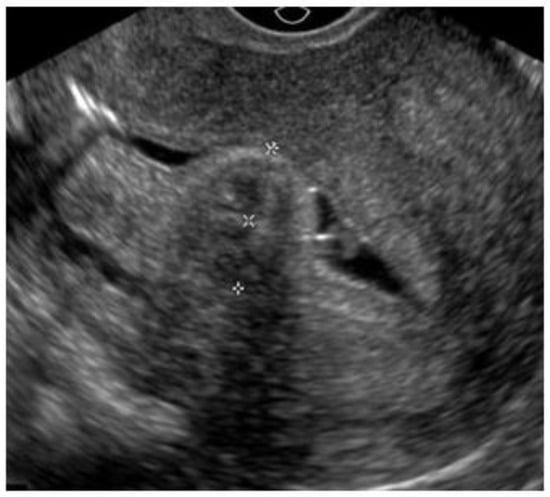

Ultrasonography (USG), especially transvaginal ultrasound (TVUS), is the routine exam and is usually the first one performed; it has good accuracy, easy access, and low cost, but it has a limited role in the presence of a large uterus or multiple nodules, as posterior acoustic shadowing makes it difficult to evaluate and count them. It is important in the evaluation of the intramural component of the myoma and the free myometrial mantle up to the serosa, but it is operator-dependent (Figure 2).

Figure 2. Submucous myoma on ultrasound. * Submucosal fibroid.